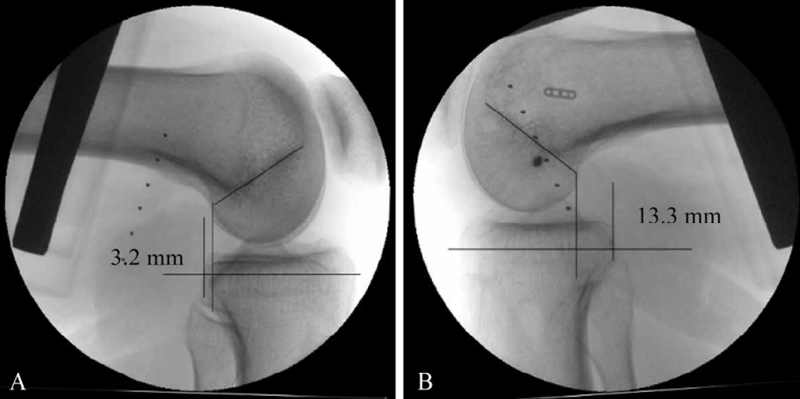

后方应力位或跪位X线检查是诊断PCL损伤的可靠方法(图6),对比健侧,后移增加0~7mm为PCL部分损伤(图7),8~11mm为单纯PCL全部断裂(图8),12mm以上可能为PCL和PLC等其他结构合并损伤(图9)。

图9 PCL完全断裂合并PLC损伤X线影像

应力位X线片示患侧(B)胫骨后移超过健侧(A)13.5mm